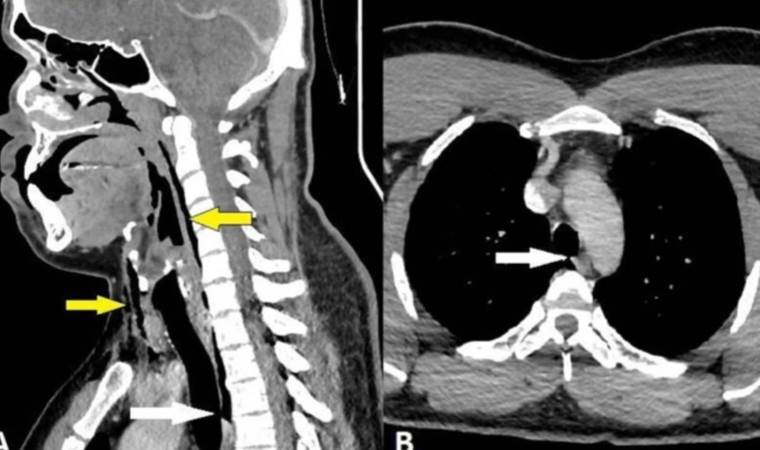

Röntgen çekildikten sonra, "cerrahi amfizem" adı verilen ve havanın kişinin vücudundaki en derin dokunun altında sıkışıp kalabildiği bir rahatsızlığı olduğu anlaşıldı. Hava, adamın boynundaki omurların yanı sıra göğsü ile akciğerleri arasındaki boşlukta sıkışıp kalmıştı.